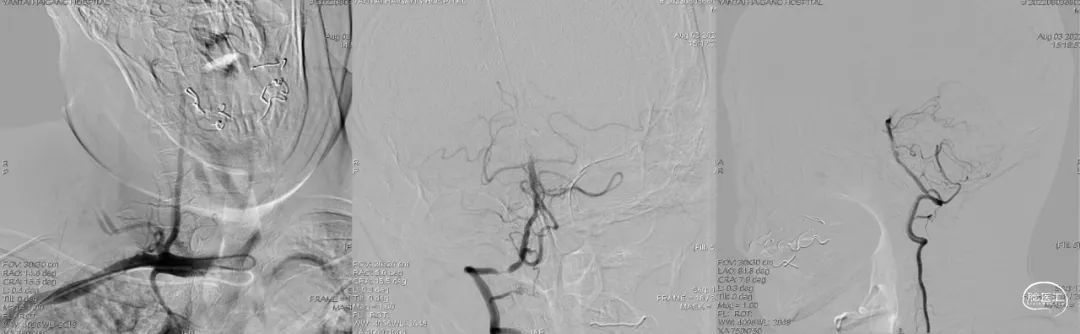

术前造影:

左椎动脉+左颈动脉造影:

右椎动脉造影:

右颈动脉造影:

右椎动脉动脉正侧位: